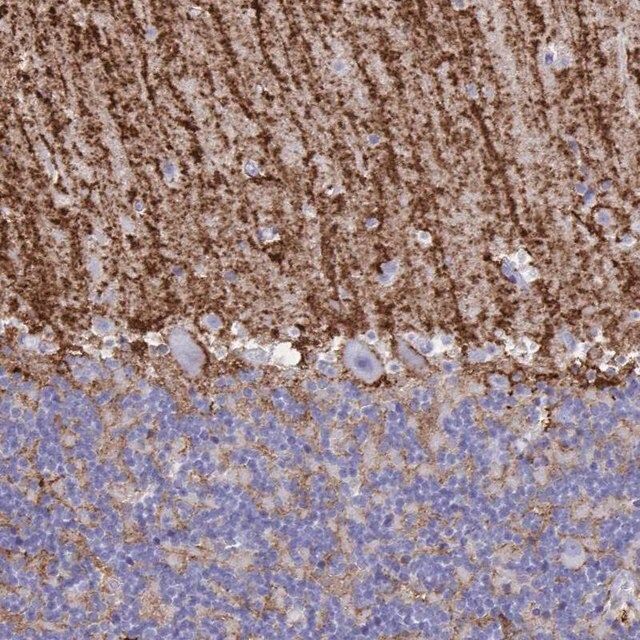

水通道蛋白 4 (aquaporin 4,AQP4) 是一种内源性蛋白,属于水通道蛋白家族,由 13 个成员组成。该基因位于人类 18 号染色体 q11-q12,有 4 个外显子和 3 个内含子。编码的蛋白有 5 个环,由 6 个跨膜结构域干预。环 A、C 和 E 面向浆外区,环 B 和 D 存在于胞浆区。在肺、胃和肾等外周器官中表达。是中枢神经系统表达的主要水通道。它由星形胶质细胞表达,并优先定位于星形胶质细胞的终足突起。它以两种可变剪接形式存在— 长的称为 M1,短的称为 M23。

人类蛋白质图谱项目可细分为三个方面的工作:人类组织图谱、癌症图谱和人类细胞图谱。支持 Tissue and Cancer Atlas 项目而产生的抗体,已经通过免疫组化针对数百个正常和疾病组织进行了测试,通过 Human Cell Atlas 项目最近的努力,很多已经通过免疫荧光法进行了表征,不仅在组织级别,现在也在亚细胞级别绘制了人类蛋白质组图谱。通过点击图像库链接,可以在 Human Protein Atlas (HPA) 位点上查看这些图像和这个庞大数据集的集合。要查看这些协议 和其他有关 Prestige 抗体和 HPA 的有用信息,请访问sigma.com/prestige。

水通道蛋白 4 (aquaporin 4,AQP4) 是脑内主要的水转运体,被认为是维持脑内水分稳态的重要物质。因此,AQP4 可能在脑水肿的发病机制中起重要角色。研究显示,这种转运体在脑缺血中过度表达。因此,它可能有潜力成为缺血性脑水肿的治疗靶点。该基因多态性与脑损伤反应和脑外伤患者的临床预后相关。AQP4 的短亚型 (M23) 有利于颗粒正交排列 (orthogonal array of particles,OAP) 的形成,OAP 的大小由短 (M23):长 (M1) 亚型的比例决定。已知这些 OAP 与视神经脊髓炎 (NMO) 中产生的致病性自身抗体相互作用。因此,对该蛋白的进一步研究可能为 NMO 的发病机制和治疗提供见解。

- 44例正常人类组织以及20例最常见癌症类型组织的IHC组织阵列。